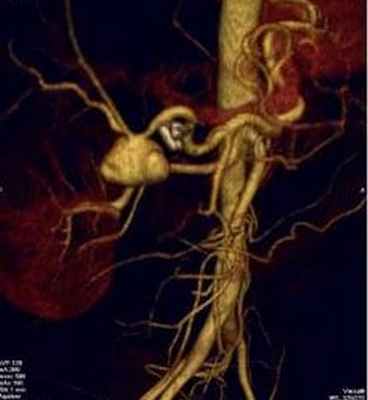

Представлен клинический случай успешного эндоваскулярного лечения ложной аневризмы печеночной артерии (больной за полгода до операции переносил лапароскопическую гастрэктомию, холецистэктомию с лимфодиссекцией по поводу аденокарциномы желудка).

Материалы и методы: больной Е., 61 год. В анамнезе язвенная болезнь желудка 8 лет. В 2013 г. выявлена аденокарцинома тела желудка, T4N0M0, выполнена лапароскопическая гастрэктомия, холецистэктомия, лимфоаденодиссекция D2 (январь 2014 г.). Послеоперационный период осложнился тромбозом левой ветви воротной вены, наружным желчным свищем, поддиафрагмальным абсцессом слева, который был дренирован. При обследовании по данным КТ-ангиографии − аденома левого надпочечника и аневризма собственной печёночной артерии. При селективной артериографии аневризма общей печёночной артерии в средней порции размерами 10´20 мм. Лечение было двухэтапным. Первоначально были использованы спирали Azur -18, но попытка не увенчалась успехом – полость аневризмы не затромбировалась. Вторым этапом установлен стент-графт в печеночную артерию.

Результаты: имплантация выполнена без осложнений, аневризма выключена из кровотока. Пациент выписан в удовлетворительном состоянии, дополнительных оперативных вмешательств не требовалось. Через 3 месяца выполнена контрольная артериография, при которой выявлен тромбоз эндопротеза. Но при этом кровоснабжение печени осуществлялось через коллатеральные ветви.

Больной Е., 61 год, поступал в ГКБ № 57 г. Москвы в плановом порядке 15.05.2014. При поступлении жалоб не предъявлял. Из анамнеза страдает язвенной болезнью желудка 8 лет. В 2013 г. выявлена аденокарцинома тела желудка, T4N0M0, выполнена лапароскопическая гастрэктомия, холецистэктомия, лимфоаденодиссекция D2 (январь 2014 г.). Послеоперационный период осложнился тромбозом левой ветви воротной вены, наружным желчным свищем, поддиафрагмальным абсцессом слева, который был дренирован. При обследовании по данным КТ-ангиографии выявлена аденома левого надпочечника и аневризма собственной печеночной артерии. Госпитализирован для дообследования и решения вопроса об оперативном лечении. При УЗИ лоцировать аневризму печеночной артерии четко не удалось. В плановом порядке выполнена селективная артериография, при которой выявлена аневризма общей печеночной артерии в средней порции, 10´20 мм (рис. 1). Диагноз подтвержден при КТ с контрастированием. Пациенту было решено выполнить оперативно лече-ние – эмболизацию псевдоаневризмы. 29.05.2014 г. левым трансаксилярным доступом установлен интродьюсер 6F. Селективно в стволе чревного ствола установлен гайд-катетер 6JR. Суперселективно проводник 0,014” проведен в полость аневризмы. Установлены две спирали Azur-18 (Terumo), 0,4´4 см и 0,8´14 см. Через 20 мин. выполнена контрольная ангиография − тромбоз основной полости аневризмы на 90% (рис. 2). Послеоперационный период протекал без осложнений. Жалобы пациент не предъявлял. Учитывая широкую шейку аневризмы и возможность миграции спиралей от дальнейшей эмболизации решено отказаться.

С целью контроля остаточной полости псевдоаневризмы пациенту через 8 дней была выполнена повторная артериография. Выявлено, что аневризма в области шейки не тромбирована, спирали Azur -18 располо-жены вне зоны контрастирования псевдоаневризмы (рис. 3). Подтекания контрастного вещества за пределы аневризмы и артерии не выявлено. Ангиографическая картина расценена, как миграция спиралей Azur -18 из контрастированного сегмента аневризмы в тромботические массы псевдоаневризмы периартериального пространства. Было решено выполнить имплантацию стент-графта. Из левого трансаксилярного доступа установлен интродьюсер 6F. Селективно в чревный ствол установлен гайд-катетер 6JR. Проводник Asashi 0,014’’ проведен в дистальную порцию ветви печеночной артерии. По проводнику без технических проблем проведен стент-графт 4,0 ´18,0 мм (Boston Sientiphic) и раскрыт в зоне шейки аневризмы под давлением 8 атмосфер. Контрольная артериография: аневризма не контрастируется, затеков контрастного вещества не отмечается (рис. 4). Послеоперационный период протекал без осложнений. Больной выписан на 3 сутки в удовлетворительном состоянии. Через 3 мес. пациент повторно был госпитализирован для выполнения контрольной артериографии. Жалобы пациент не предъявлял. Выявлено, что общая печеночная артерия не контрастируется в проксимальной трети (2 см) – тромбоз стент-графта. Однако дистальные отделы печеночной артерии заполняются по коллатеральным ветвям (рис. 5).

Jecko V. с соавт. описали разрыв печеночной артерии после оперативного вмешательства по поводу люмбалгии, который привел к смерти пациентки [10], Fatic N. с соавт. выполнили успешное протезирование печеночной артерии после резекции желудка по Бильрот-II [11]. Asai K. с соавт. произвел эндопротезирование ложной аневризмы печеночной артерии после панкреато-дуоденальной резекции у больной по поводу холангиокарциномы [12]. Lü P.H., Zhang X.C., Wang L.F. описывают 8 случаев использования стент-графта для выключения ложной аневризмы печеночной артерии. У 6 из них осложнения в ближайшем послеоперационном периоде не наблюдались, у 1 больного – окклюзия печеночной артерии, у 1 пациента – вазоспазм и эндолик. Этим больным процедура дополнялась установкой спиралей в просвет артерии. Оценка результатов произведена через 14 мес., стенозы или тромбозы стентов не выявлены [13]. Суворова Ю.А. и соавт. считают рентгенэндоваскулярный гемостаз с помощью стент-графта методом выбора в лечении массивного послеоперационного кровотечения из магистральных артерий (в том числе общей печеночной), особенно у больных с высоким хирургическим риском. Описано 2 случая успешного эндопротезирования общей печеночной артерии [14]. Также описано успешное эндопротезирование аневризмы селезеночной артерии [15]. В сентябре 2014 г. на ежегодном конгрессе эндоваскулярных хирургов CIRSE в Глазго (Великобритания), Sundeep Punamia, был опубликован стендовый доклад, в котором автор описал возможность эмболизации псевдоаневризмы печеночной артерии из чрескожно чреспеченочного доступа. Эта методика предлагается при окклюзии общей печеночной артерии, когда нет возможности выполнить эмболизацию антеградным доступом [16]. В представленном клиническом наблюдении выполнена успешная имплантация стент-графта в печеночную артерию при ложной (посттравматической) аневризме с хорошим клиническим результатом. Ангиографические результаты эндопротезирования неоднозначны в данном случае. С одной стороны после успешной имплантации произошел его тромбоз в ближайшем послеоперационном периоде. С другой стороны тромбоз стент-графта не привел к нарушению кровоснабжения печени в бассейне общей печеночной артерии из-за развития хороших коллатеральных сосудов. В итоге полость псевдоаневризмы выключена из кровотока без дефицита кровоснабжения печени. Минимальная инвазивность операции основной положительный момент для данного пациента, так как альтернативой являлось протезирование печеночной артерии через лапаротомный доступ, что тяжело выполнимо с технической точки зрения и неблагоприятно для самого пациента в связи с выраженным рубцовым процессом в верхнем этаже брюшной полости. Выполненное стентирование позволило пациенту проводить дальнейшее лечение по онкопрограмме без риска для жизни со стороны сосудистых осложнений. Лечение ложной аневризмы печеночной артерии является редким малоизученным ятрогенным осложнением различных хирургических вмешательств и требует дальнейшего изучения.